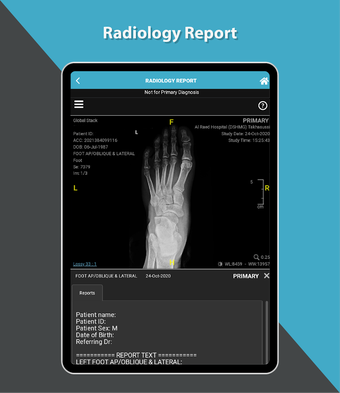

これは、Dr. Sulaiman Al-Habib Medical Services Groupが提供するすべてのサービスにアクセスするのを助ける無料のアプリです。グループの持続的なデジタル変革の重要な部分であり、効率と生産性の向上を重視しています。この新しいアプリは、オンライン医師相談から医療検査や放射線学の報告書まで、グループが提供するすべてのサービスに簡単にアクセスできるようになります。また、あなたと家族の医療記録を閲覧する機会も提供しています。